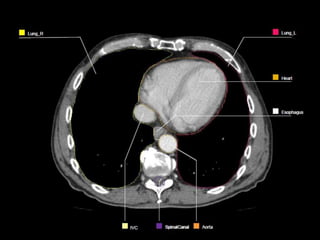

OARs  Liver  Kidney Stomach  Spinal Cord  Heart  Duodenum  Small Bowel  Lungs